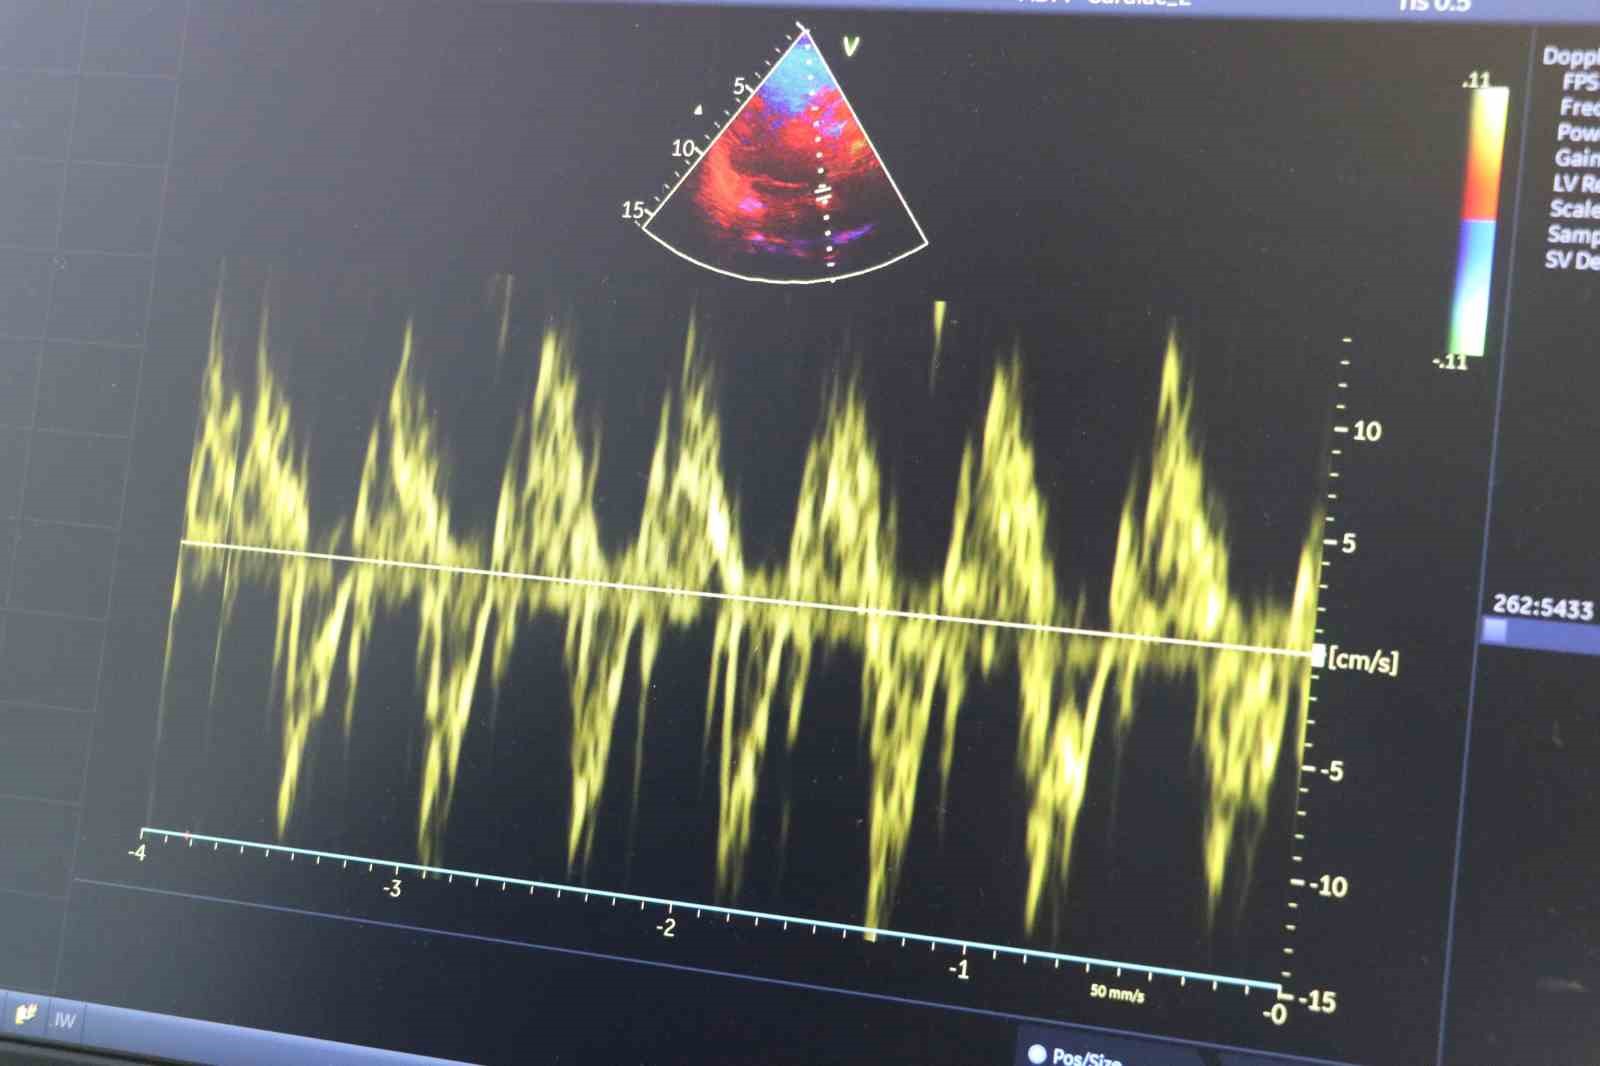

Kış aylarının gelmesiyle birlikte düşen hava sıcaklıkları, kalp ve damar hastalıkları olan bireyler için önemli riskler oluşturuyor. Soğuk havada damarlarda meydana gelen büzüşmenin (vazokonstriksiyon) kalp hızını artırarak tansiyon yükselmesine sebep olabiliyor. Yetersiz sıvı tüketimi nedeniyle kan yoğunluğunun artması da kalp damar sistemi üzerinde ek bir yük oluşturuyor. Adrenalin gibi hormonların artışı, kalp hızını yükselterek stres düzeyini artırırken göğüs ağrısı ve nefes daralması riskini de çoğaltıyor. Stent takılmış, bypass operasyonu geçirmiş, hipertansiyon hastası, kolesterolü yüksek, ileri yaşta olan ve sigara kullanan bireylerin soğuk havalarda daha dikkatli olmaları gerekiyor. Bu kişilerin aşırı efor gerektiren aktivitelerden uzak durmaları, kalın giyinmeleri ve mümkünse çok soğuk havalarda dışarı çıkmamaları öneriliyor. Ayrıca soğuk havalarda azalan sıvı tüketiminin artırılması da önem taşıyor. Uzmanlar tarafından beslenme açısından tuzlu ve yağlı gıdalardan uzak durulması, lifli gıdalar, sebze ve balığın tercih edilmesi gerektiği ifade ediliyor. Konuya ilişkin açıklamalarda bulunan Sivas Medicana Hastanesi Kalp Damar Hastalıkları uzmanı Doç. Dr. Hasan Yücel, soğuk havalarda vücut ısısının düşmesiyle damarlarda belirgin bir büzüşme yaşandığını belirterek, "Kalp damar hastalığı olan bireylerin hem yaşam tarzına hem de beslenmelerine daha fazla dikkat etmeleri büyük önem taşıyor" dedi.

Soğuk havalarda kalbin daha fazla zorlandığını ifade eden Hasan Yücel, "Kış aylarının gelmesiyle kalp damar rahatsızlıkları olan hastalarımızın soğuk havalarda kalplerine daha fazla özen göstermeleri gerekiyor. Özellikle soğuk havalarda damarlarda bizim vazokonstriksiyon dediğimiz damar büzüşmesi olayı, kalp hızının artışına, tansiyon yükselmesine ve kalbin zorlanmasına sebebiyet vermektedir. Ayrıyeten yeterli sıvı alınmamasından dolayı damarlar içindeki kan yoğunluğunun artması, damar rahatsızlıkları olan hastalarımızı kötü etkilemektedir. Damarların büzüşmesi, kasılması olayı kış aylarında daha belirgin olmakta, bu da tansiyon artışı oranlarını yükseltmektedir. Özellikle adrenalin gibi hormonlar kalbin hızını artırıp tansiyon yükselmelerine sebebiyet vererek stres oluşturmaktadır ve hastalarımızın soğuk havalarda bunlara dikkat etmesi gerekmektedir. Kalp damar rahatsızlığı olan, damarında stent olan, baypas geçirmiş olan hastalarımızla beraber hipertansiyonu olan, kolesterolü yüksek olan, sigara içen hastalar ve yaşı ileri olan hastalar soğuk havalarda daha dikkatli olmalıdırlar. Aşırı yoğun fiziksel aktivitelerden kaçınmalıdırlar, kalın giyinmeleri gerekmekte, çok soğuk havalarda mümkünse dışarı çıkmamaları gerekmekte, ağır efor isteyen işlemler yapmamalarını istemekteyiz" dedi.

Kış aylarında kalp rahatsızlıkları olan hastaların beslenmelerine de dikkat etmesinin önemine vurgu yapan Yücel, " Kullandıkları ilaçları düzenli kullanıp doktor kontrolünü aksatmamaları gerekmektedir. Ayrıca soğuk havalarda sıvı alımı azaldığı için sıvı tüketimine dikkat etmeleri gerekmektedir. Soğuk havalarda vücut ısısını korumak önemli. Damarlarda kasılma, büzüşme (vazokonstriksiyon) oluşmakta ve kalp hızı artmakta, bu da soğuk havalarda dışarı çıktığımızda efor kapasitemizin azalmasına, nefes daralmasına ve göğüs ağrısına sebebiyet vermektedir. Beslenme noktasına da değinecek olursak, tuzlu ve yağlı gıdalardan uzak durmamız gerekmektedir. Tuz alımından sonra tansiyon yüksekliği kalbe yük oluşturmaktadır. Kanın yoğunluğunun artmasına bağlı olarak yağlı tüketimler kolesterol artışına sebebiyet vermekte, damarda plak oluşumuna ve kan akışının yavaşlamasına sebebiyet vermektedir. Yaz kış fark etmeksizin yağlı ve tuzlu gıdalardan kalp damar hastalığı olan kişilerin uzak durması gerekmektedir. Beslenme konusunda lifli gıdalar, bitki ve sebzeler tüketmemiz lazım. Balık tüketimi ve bol su tüketimine önem vermemiz gerekmektedir. Bunlara dikkat edilmediği durumlarda yeniden damar tıkanıklıkları oluşabilir, kalp spazmı dediğimiz hadiseler olabilir ve göğüs ağrısı oluşabilir. Kalp krizi, felç ve inme gibi durumlar tetiklenebilir. Kış aylarında kalp rahatsızlıkları olan hastalarımızın yaşamlarına ve beslenmelerine dikkat etmeleri, ilaçlarını düzgün kullanıp kontrollere önem vermeleri gerekmektedir" diye konuştu.